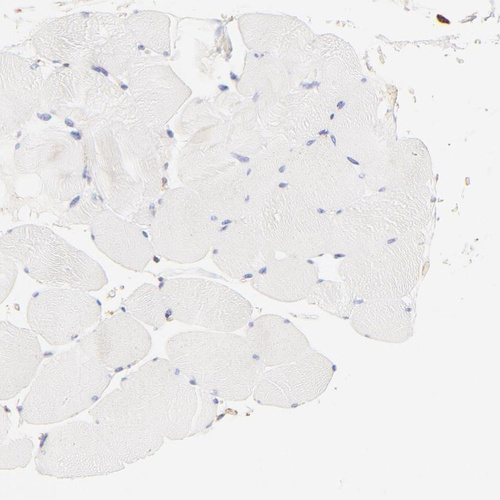

Immunohistochemistry analysis in human prostate and skeletal muscle tissues using HPA002925 antibody. Corresponding FLNA RNA-seq data are presented for the same tissues.